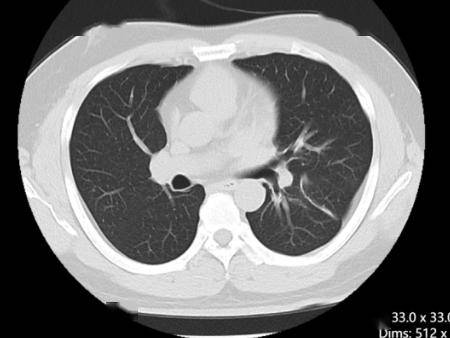

这一发现不仅为患者找到了全新的治疗方向,也填补了ALK罕见突变谱的空白。治疗团队经过充分的文献调研和多学科讨论后,决定给予患者ALK抑制剂阿来替尼靶向治疗。仅仅一个月后,复查胸部CT显示左肺上叶病灶较前明显缩小,疗效评估达到部分缓解(PR),患者的咳嗽、胸闷等症状完全消失,也摆脱了化疗带来的严重不良反应。

靶向治疗前左肺下叶肿块25mm

靶向治疗后左肺下叶肿块5mm